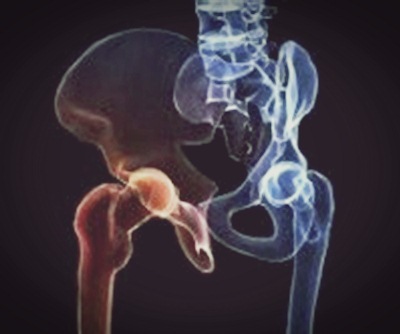

고관절의 구조를 보면 재미있는 부분이 있다. 대퇴골두라 불리는 공처럼 둥근 넓적다리뼈의 머리 부분과 이 부분을 감싸는 절구 모양으로 생긴 골반골인 비연구골로 구성되어 있다. 주로 앞뒤로 움직이는 무릎관절과 다르게 고관절의 움직임은 앞뒤, 좌우, 회전 등 움직임의 범위가 넓은 것이 특징이다.

이처럼 골반과 다리를 연결해주며, 체중 지탱과 함께 보행을 돕는 핵심적인 역할을 하기 때문에 그 구조가 안정적이다. 이런 안정적인 구조에도 불구하고 고관절 건강을 챙기지 않으면 고관절 충돌 증후군 등 관절 질환을 호소할 수 있다.